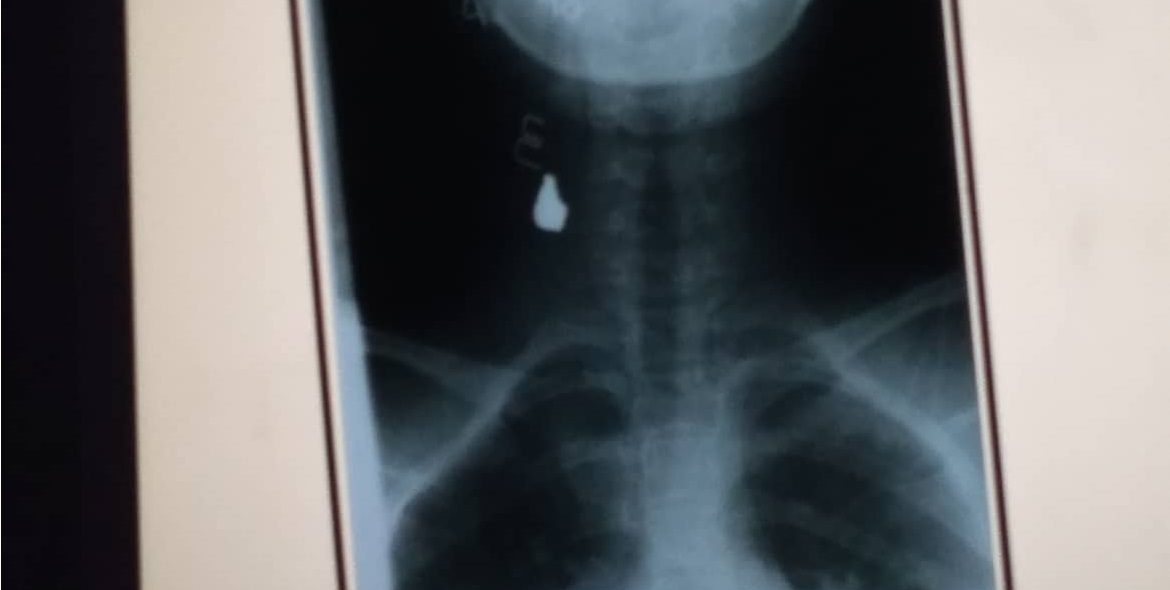

Kopya ng XRay result kung saan makikita ang lokasyon ng pumasok na bala sa may leeg ng biktima

Kinailangan umanong dalhin sa Manila ang biktimang babae dahil hindi umano kaya sa Romblon ang gagawing operation sa biktima para matanggal ang bala na bumaon sa kanyang leeg.